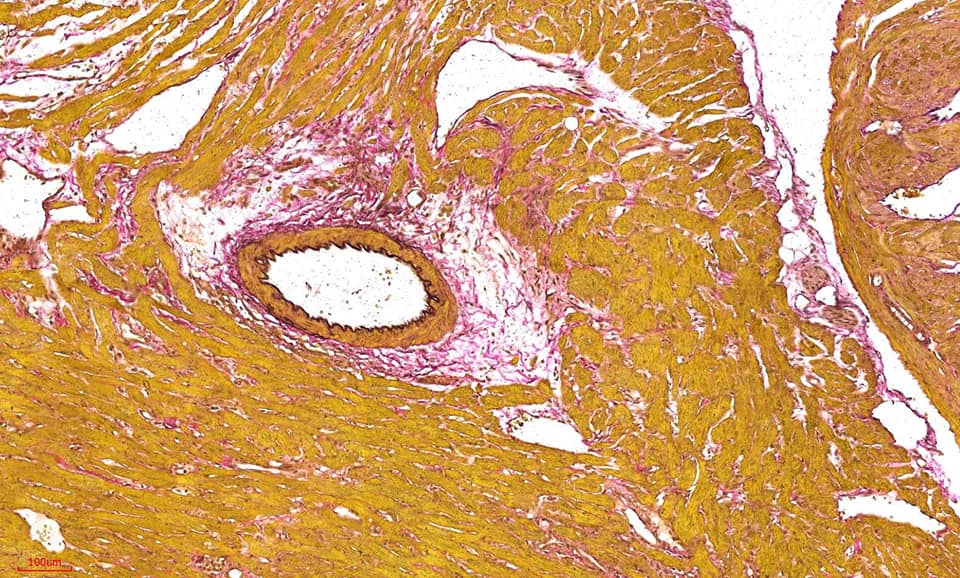

彈力纖維(Verhoeff’s Van Gieson,EVG)染色,彈性纖維廣泛分佈與身體各處,特別在動脈壁、肺泡壁和皮膚中最為豐富。觀察組織內彈性纖維是否有增生或斷裂崩解等。

組織被含有三氯化鐵和碘的蘇木精染色再用過量的媒染劑三氯化鐵中斷組織與染料的結合,染料被分化液中的大量媒染劑吸引,使其從組織中清除。彈性纖維對鐵蘇木精具有較強的吸引力使染料能比其他組織保留更久而達到染色的效果。彈性纖維黑色,膠原纖維為紅色,背景為黃色。

Miller’s Elastic Stain ( E.V.G stain) 實際染色範例

※結果觀察:

彈力纖維呈藍黑色,肌纖維、纖維素、神經膠質呈黃色,膠原纖維呈紅色,胞核呈藍色